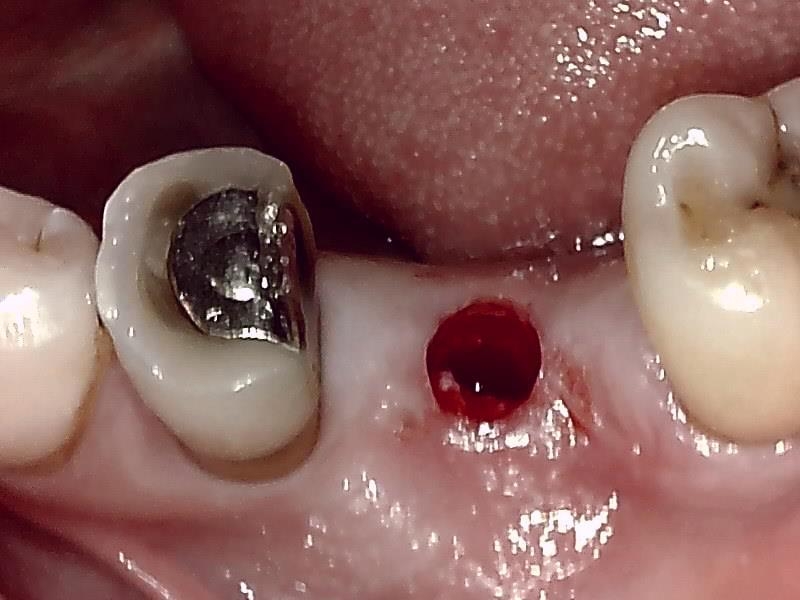

術前の顎堤

顎堤歯肉をくり抜き切開して歯肉片を温存する。

顎堤部 歯槽骨にドリリングする。

インプラント体の口径に合わせて埋入孔を形成した状態です。